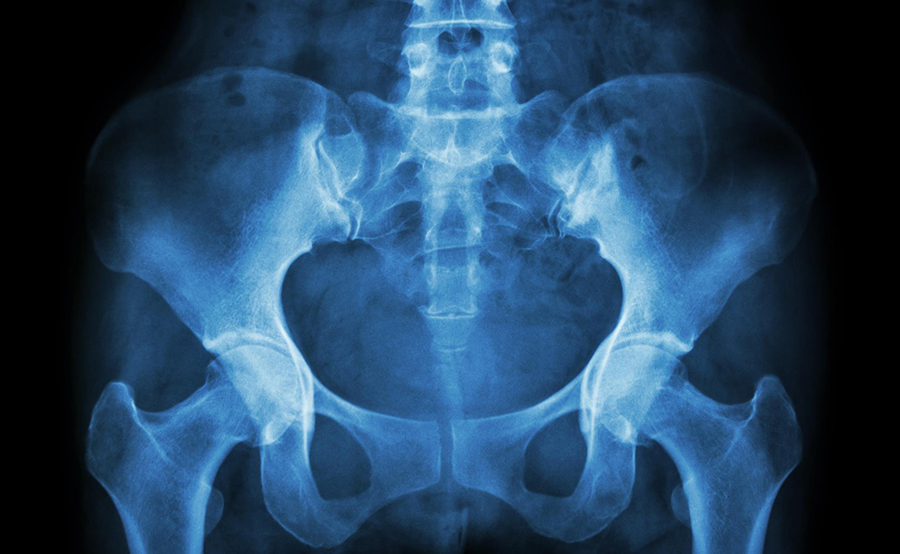

Bekkenleddsmerter rammer ca. 12 000 gravide kvinner hvert år. De aller fleste blir bra like etter fødsel, men mellom 2 000 – 4 000 fortsetter å ha plager også etter fødselen, og vil ha behov for helsetjenester.